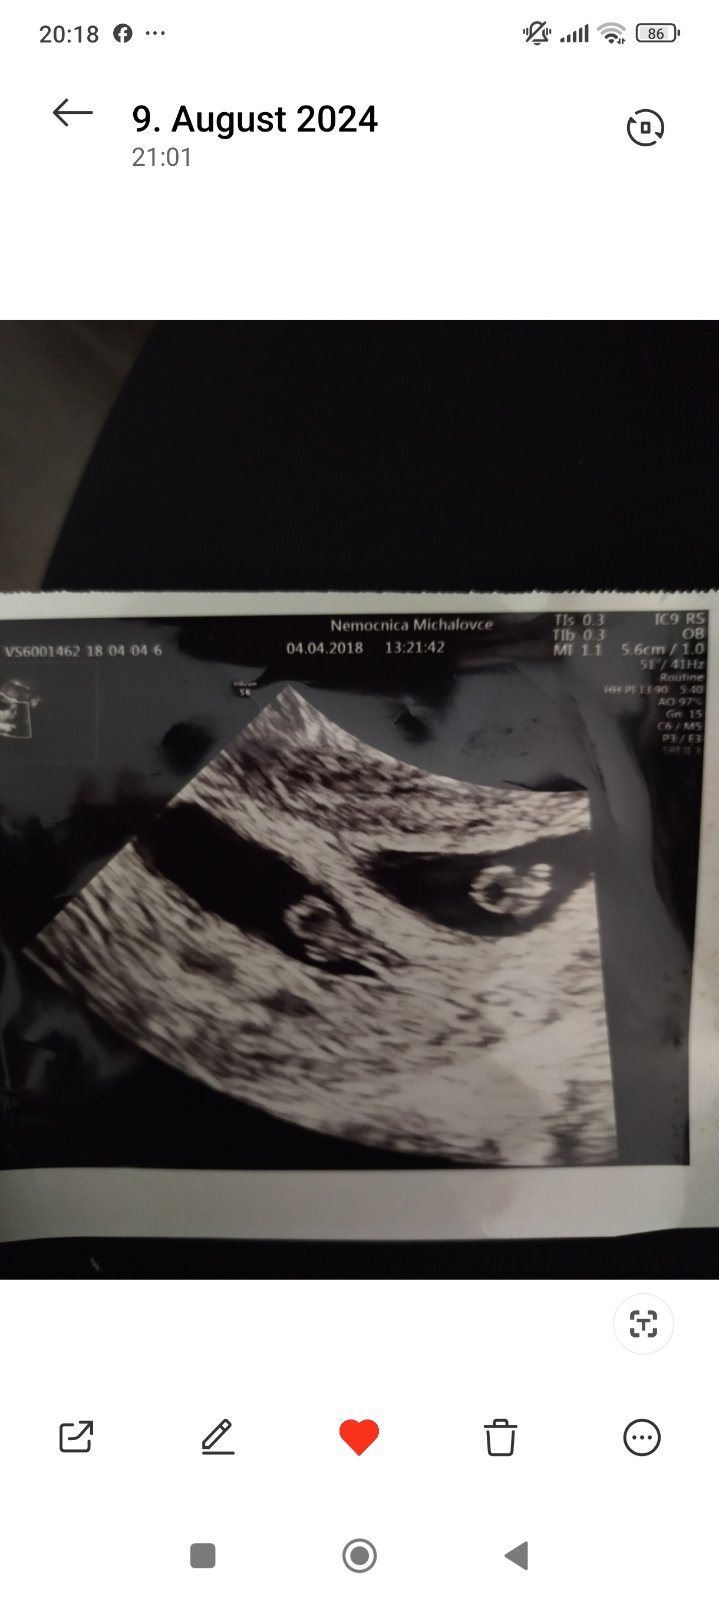

Dvojicky by lekar na sone uz mohol vidiet, zalezi od kvality pristroja. Ja som bola na pohotovosti 5+2, lekarka videla len jeden prazdny vak. Na druhy den mi robil sono moj lekar a videl dva plody. Obidva s akciou srdiecka. Vytok - momentalne ti nik nepovie 100%, z coho moze byt. Moze to byt roztahovanie maternice, aj nieco horsie. V tych prvych tyzdnoch je to take neiste. Drzim palce, nech vsetko dobre dopadne.